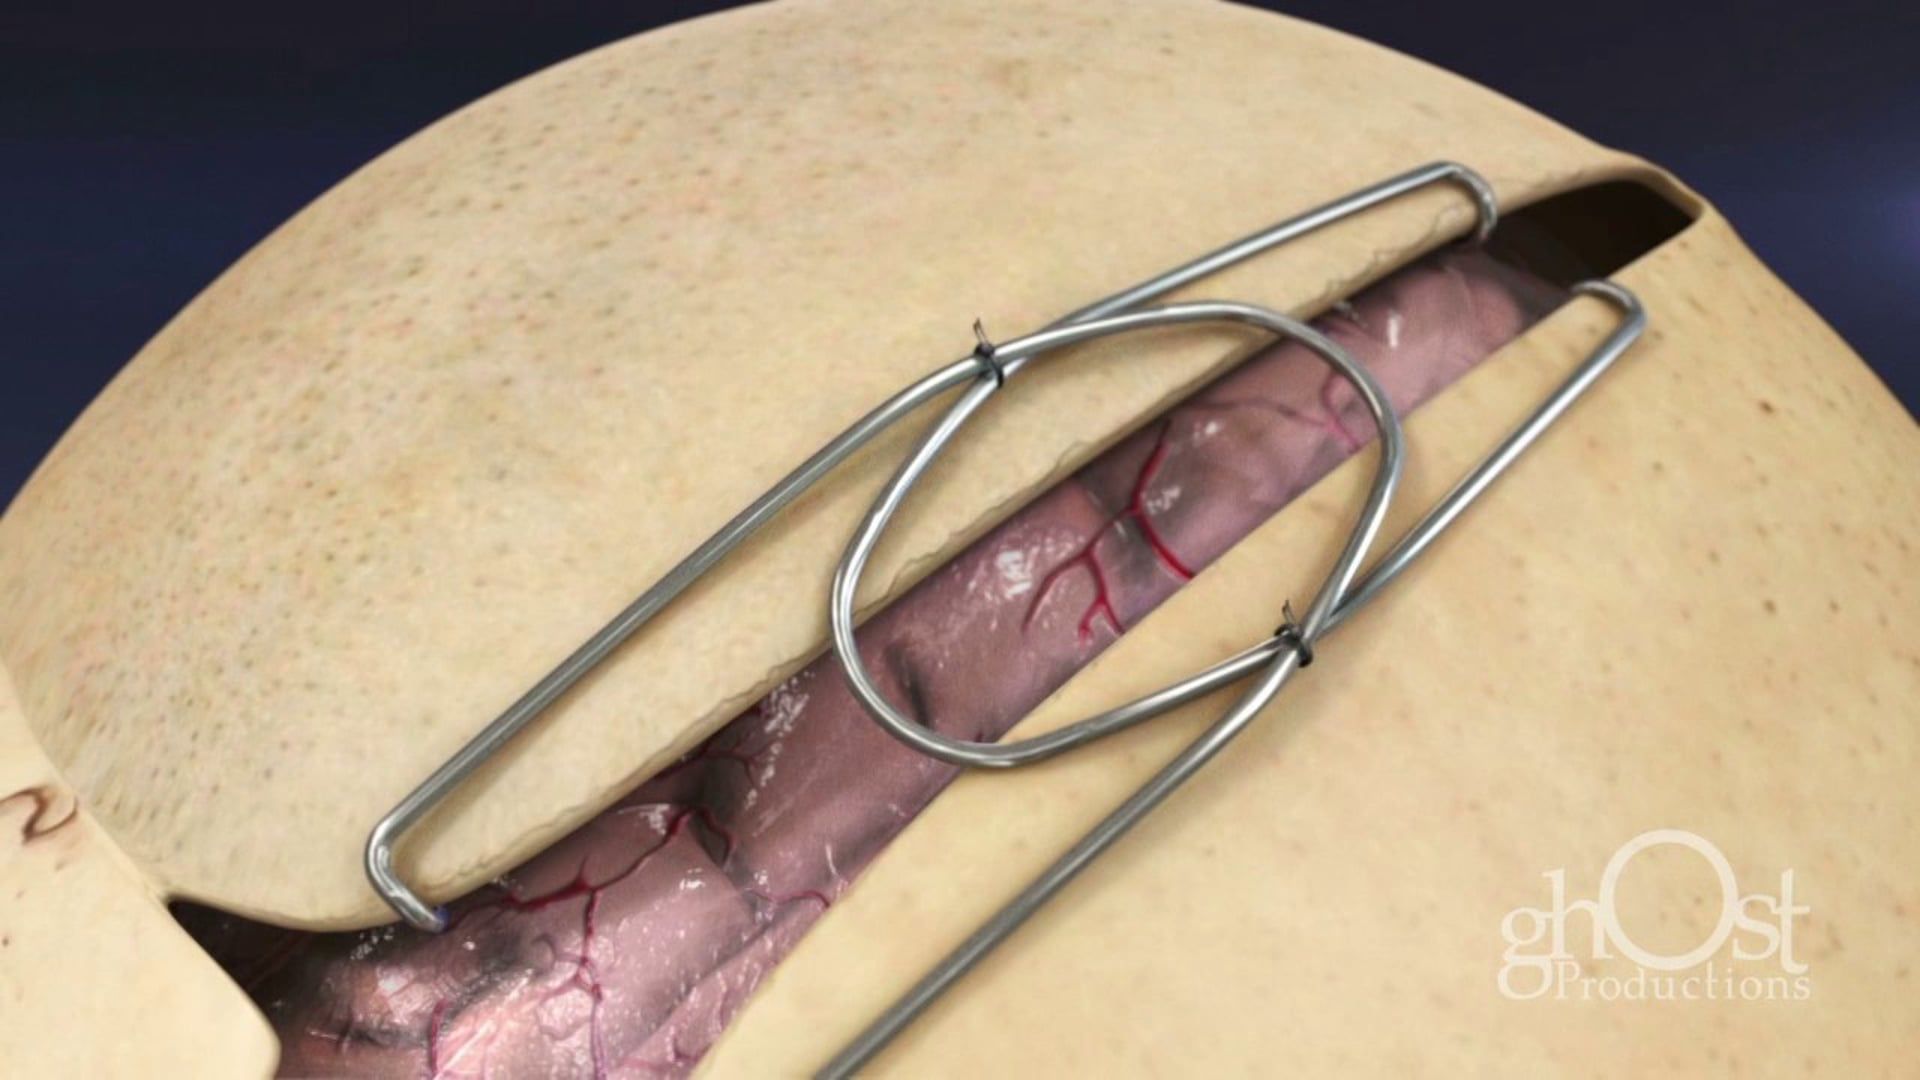

Medical Animation

Neurology